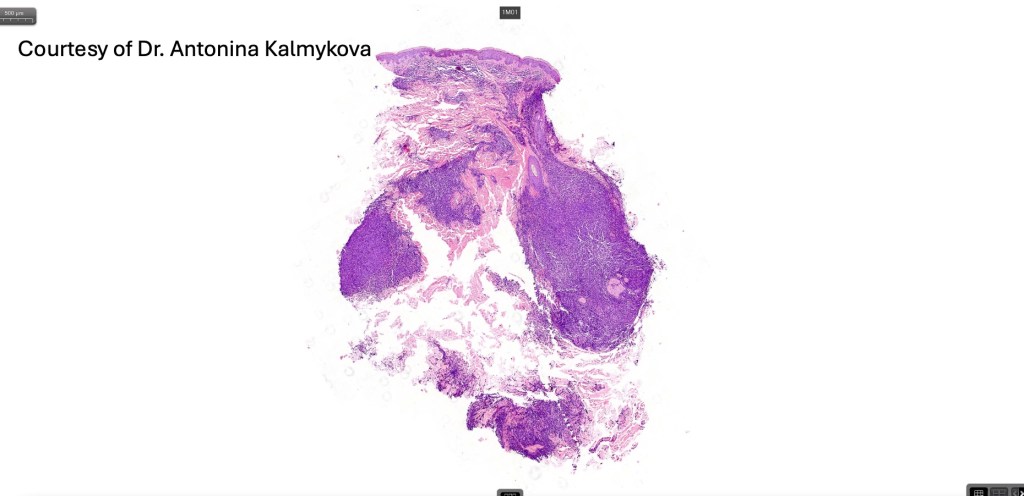

Histological features

. No epidermal involvement

. Dermal +/- subcutaneous fat infiltrate

. No angioinvasion or angiodestruction